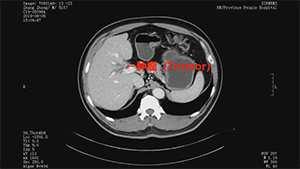

腹腔镜Ⅲb型肝门胆管癌根治术

作者:蔡翊 | 作者单位:湖南省人民医院

发布时间:2020-09-03 22:17:01